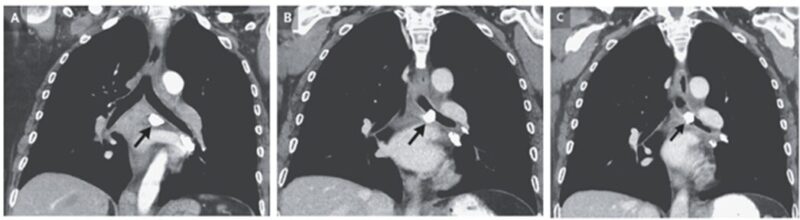

アスベスト肺による収縮性心膜炎:両心カテーテル検査にて心室の相互依存性と圧力とレースの不一致を認めた症例

69歳女性。 3年にわたる労作時呼吸困難が悪化したため救急外来を受診した。 断熱材製造会社での勤務中に発生したアスベスト暴露に起因すると考えられる限局性胸膜プラ…